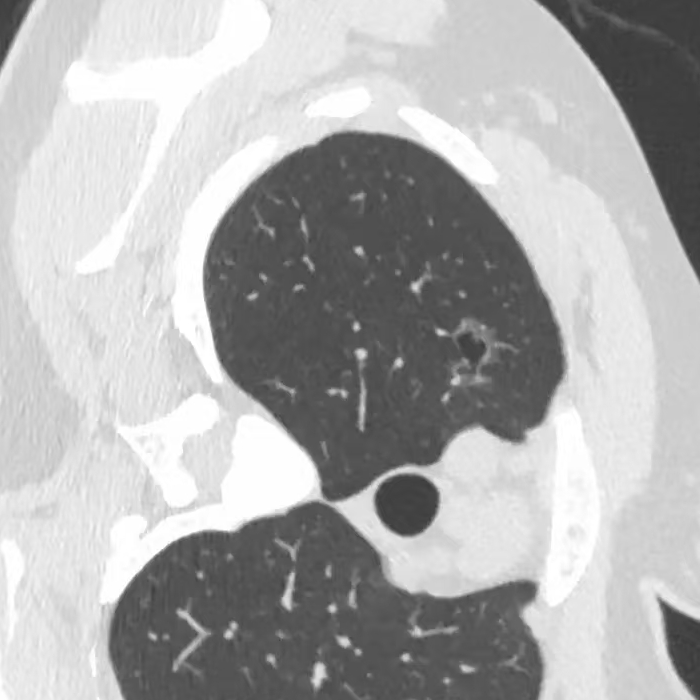

健康直通车: 健康是生命的宝贵财富,也是幸福生活的基石。为了更好地服务广大百姓,传播健康知识,葫芦岛市第二人民医院推出“健康直通车”专题栏目,将专业的医学知识以通俗易懂的方式传递给每一位市民,掌握科学的疾病预防方法,共同构筑健康中国的坚实基石。 什么是肺结节 肺结节是指肺内直径小于或等于3cm的类圆形或不规则形病灶,影像学表现为密度增高的阴影。大于3cm的称肿块。肺结节依其密度不同可分为实性结节、部分实性结节、磨玻璃结节,其中部分实性结节的恶性可能性最大,磨玻璃结节次之,实性结节尤其是小的实性结节结节最可能是良性的。 肺结节的常见病因 1、良性(约90%) 🔸 感染:结核、真菌、细菌性肺炎后遗留的瘢痕; 🔸 非感染:错构瘤(良性肿瘤)、炎性假瘤、血管瘤等。 2、恶性(约10%) 🔸原发性肺癌(如腺癌、鳞癌); 🔸转移性肿瘤(其他器官癌症转移至肺)。 如何根据影像判断肺结节性质 1、依据结节大小判断 🔸小于0.5cm的肺结节绝大多数都是良性的,属于微小结节。即使部分小于0.5cm肺结节是恶性的,但是适当的观察不影响预后。每年复查一次胸部CT就可以。 🔸大于0.5cm持续存在的纯磨玻璃结节,观察6个月,若持续存在,不管有无进展均多数是恶性的,视患者意愿,手术可以立即做也可观察至进展再做,不影响预后。 🔸大于0.8cm的部分实性结节恶性可能性非常大,应积极评估结节边缘毛刺、分叶、胸膜凹陷等征象。 🔸若实性部分大于0.5cm,恶性率显著提高。若在3~6个月随访期间实性部分增大或者总体部分增大,都可以考虑手术切除。而即使小于0.8cm的部分实性结节也需3个月就复查对比。 2、依据肺结节形态 如CT上提示病灶形态不规则、毛刺、分叶、胸膜凹陷、空泡征、血管集束征等,符合恶性肿瘤的征象。 🔸结节与正常肺组织之间界限非常清楚的恶性可能性大。 🔸结节密度不均呈混杂密度或均匀较大纯磨玻璃结节也基本是恶性的。 🔸有胸膜牵拉(不管是肺表面的脏层胸膜还是叶间裂部位的胸膜)的恶性可能性大。 🔸结节有浅分叶、细毛刺,密度较高而与周围肺组织边界不清的恶性可能性大。 🔸磨玻璃或混合磨玻璃结节存在小空洞的恶性可能性大。 🔸影像上似慢性炎表现,而没有炎症相关的其他异常,特别当所谓炎症区域内部或一侧与正常肺组织之间界限非常清楚的基本上是恶性的。 3、从结节发展情况来看 所有随访中增大进展的都需要考虑恶性可能,不进展而持续存在的纯磨玻璃结节也需考虑恶性。 葫芦岛市第二人民医院肺结节诊治中心孙振教授深耕肺结节领域四十余载,凭借对临床实践的执着钻研与深厚积淀,在肺结节精准诊断及鉴别诊断领域形成独到见解。他系统总结海量临床病例,创新性提炼出一套科学化、规范化的肺结节全周期诊疗体系,尤其在早期微小结节的影像特征识别、良恶性风险分层等方面积累了丰富经验,为众多患者提供了精准、高效的诊疗方案。 人民医院·人民名医 孙振 主任医师 三级教授 ·葫芦岛市第二人民医院胸外科主任、肺结节诊治中心主任 ·中国医科大学客座教授 ·原央企总医院著名胸外科专家 ·辽宁省医学会胸外科委员 ·辽宁省抗癌协会肺癌专业委员会委员 ·辽宁省细胞生物学学会食管癌专业委员会理事 ·主持多项科研成果获科技成果奖、科技进步奖、国家专科奖项 医学成就 从事胸外科临床工作近40年,担任胸外科首席专家及科室主任20余年,是我省胸外科领军人物,推动肺癌、食管癌等胸部肿瘤外科的规范化诊疗,在央企总医院牵头成立了肺结节诊疗中心,率先开展CT引导下肺内小结节定位切除,既确切完整切除肺内小结节,又降低肺功能损害。 专业特色 擅长肺癌、食管癌的外科手术和综合治疗,在各类高难度胸外伤手术治疗、胸腔镜微创手术、胸腺瘤手术及复杂并发症处理方面具有高深造诣,尤其擅长肺癌早期诊断,胸部小结节CT早期肺癌的鉴别等。完成各类高难度胸外科手术5000余例,其中微创手术占比达90%,治愈率达98%,多项业务填补省内空白。 开展的高难手术 胸腔镜肺部结节微创手术、肺癌根治术、食管癌根治术、各种纵隔肿瘤切除术、胸骨后甲状腺手术及胸部复合性外伤的抢救手术等。